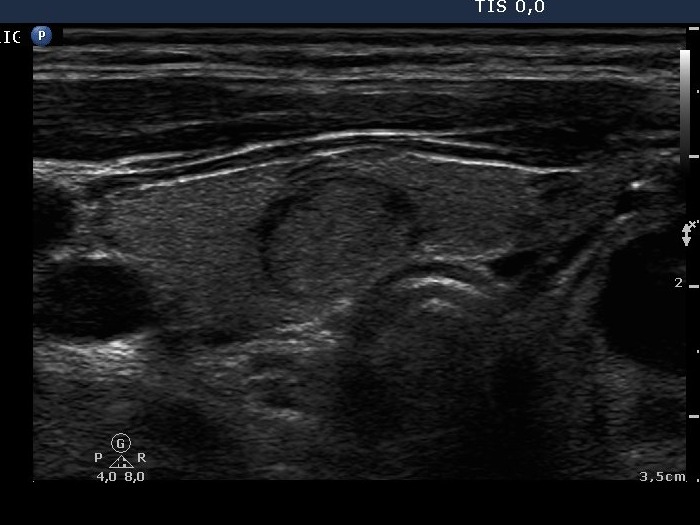

Benign Hashimoto's thyroiditis (cytological diagnosis) - case 1652

First, we demonstrate two cases of Hashimoto's thyroiditis with pronounced fibrotic changes. Both present pale and bright hyperechogenic granules and lines corresponding to normal and excessive connective tissue. Neither of the discrete areas are nodules in a pathological sense.